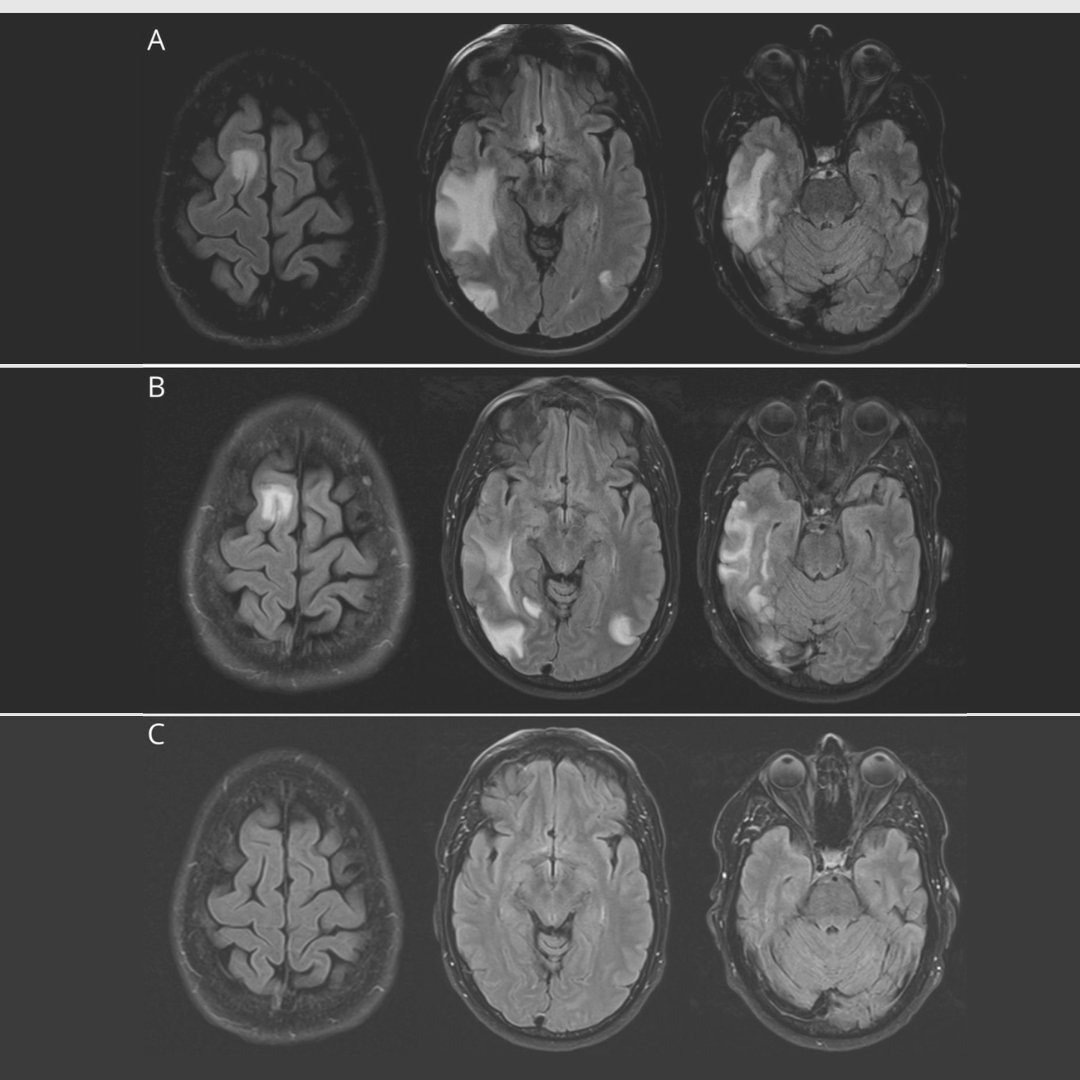

Brain resonance imaging before and after antiToxoplasma Brain Lesions And Aids Although hiv infection and aids primarily affect the immune system, they also disturb the nervous system and can lead to a wide range of severe neurological disorders, particularly if hiv goes untreated and progresses to aids. Many of the most severe neurological conditions can be prevented with antiretroviral therapy. Hiv/aids affects the cns by one of four mechanisms: Although hiv. Brain Lesions And Aids.